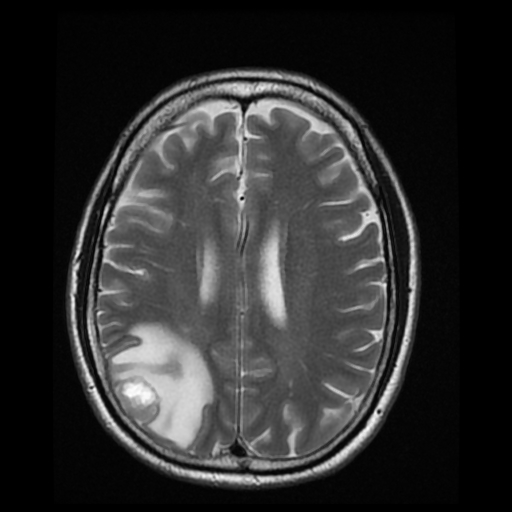

Patients with brain tumors may complain symptoms of headache, dizziness, vomiting, blurred vision, limbs weakness, etc.. Other symptoms include seizures and endocrine disorders; Personality or behavior changes may also occur. With modern advances in brain imaging technology, Computerized Tomography (CT) scan and magnetic resonance imaging (MRI) are the most commonly used diagnostic tools.

MRI does not involve radiation risk. Patients are required to lie inside the scanner with a strong magnetic field. Patients will not feel pain during the scanning process. MRI images can be achieved in a number of different angles and through a variety of different “signals”, so as to letting us to explore more about the tumors’ nature, thus allowing neurosurgeons making the most appropriate treatment plan for patients.